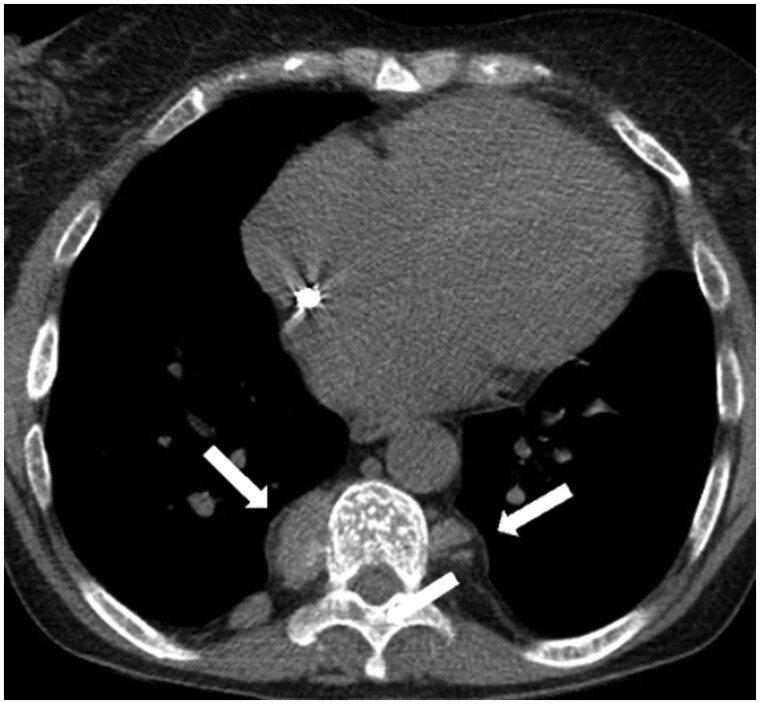

纵隔肿块是一组异质性的实体,具有多种组织病理学和放射学特征。影像学在纵隔异常的检测和解释中起着关键作用。CT仍然是首选的方式,因为它具有高空间和时间分辨率,并且能够评估组织组成,包括检测液体、脂肪和钙化。MRI在特定情况下是一种辅助工具,如区分复杂囊肿和实性病变或识别细胞内脂肪含量,如胸腺增生。纵隔肿块的鉴别诊断主要依赖于肿块的位置和组织组成,并结合患者的临床特征。这篇综述讨论了成人最常见的纵隔肿块,提供了一种主要基于优势密度模式和位置的实用方法来区分它们。

Mediastinal masses represent a heterogeneous group of entities characterized by a variety of histopathological and radiological features. Imaging plays a pivotal role in the detection and interpretation of mediastinal abnormalities. CT remains the modality of choice due to its high spatial and temporal resolution and its ability to assess tissue composition, including the detection of fluid, fat, and calcifications. MRI represents a complementary tool in specific scenarios, such as differentiating complicated cysts from solid lesions or identifying intracellular fat content, as seen in thymic hyperplasia. The differential diagnosis of mediastinal masses relies primarily on the location of the mass and tissue composition, integrated with clinical characteristics of the patient. This review discusses the most common mediastinal masses in adults, providing a practical approach to their differentiation mainly based on the predominant density pattern and location.